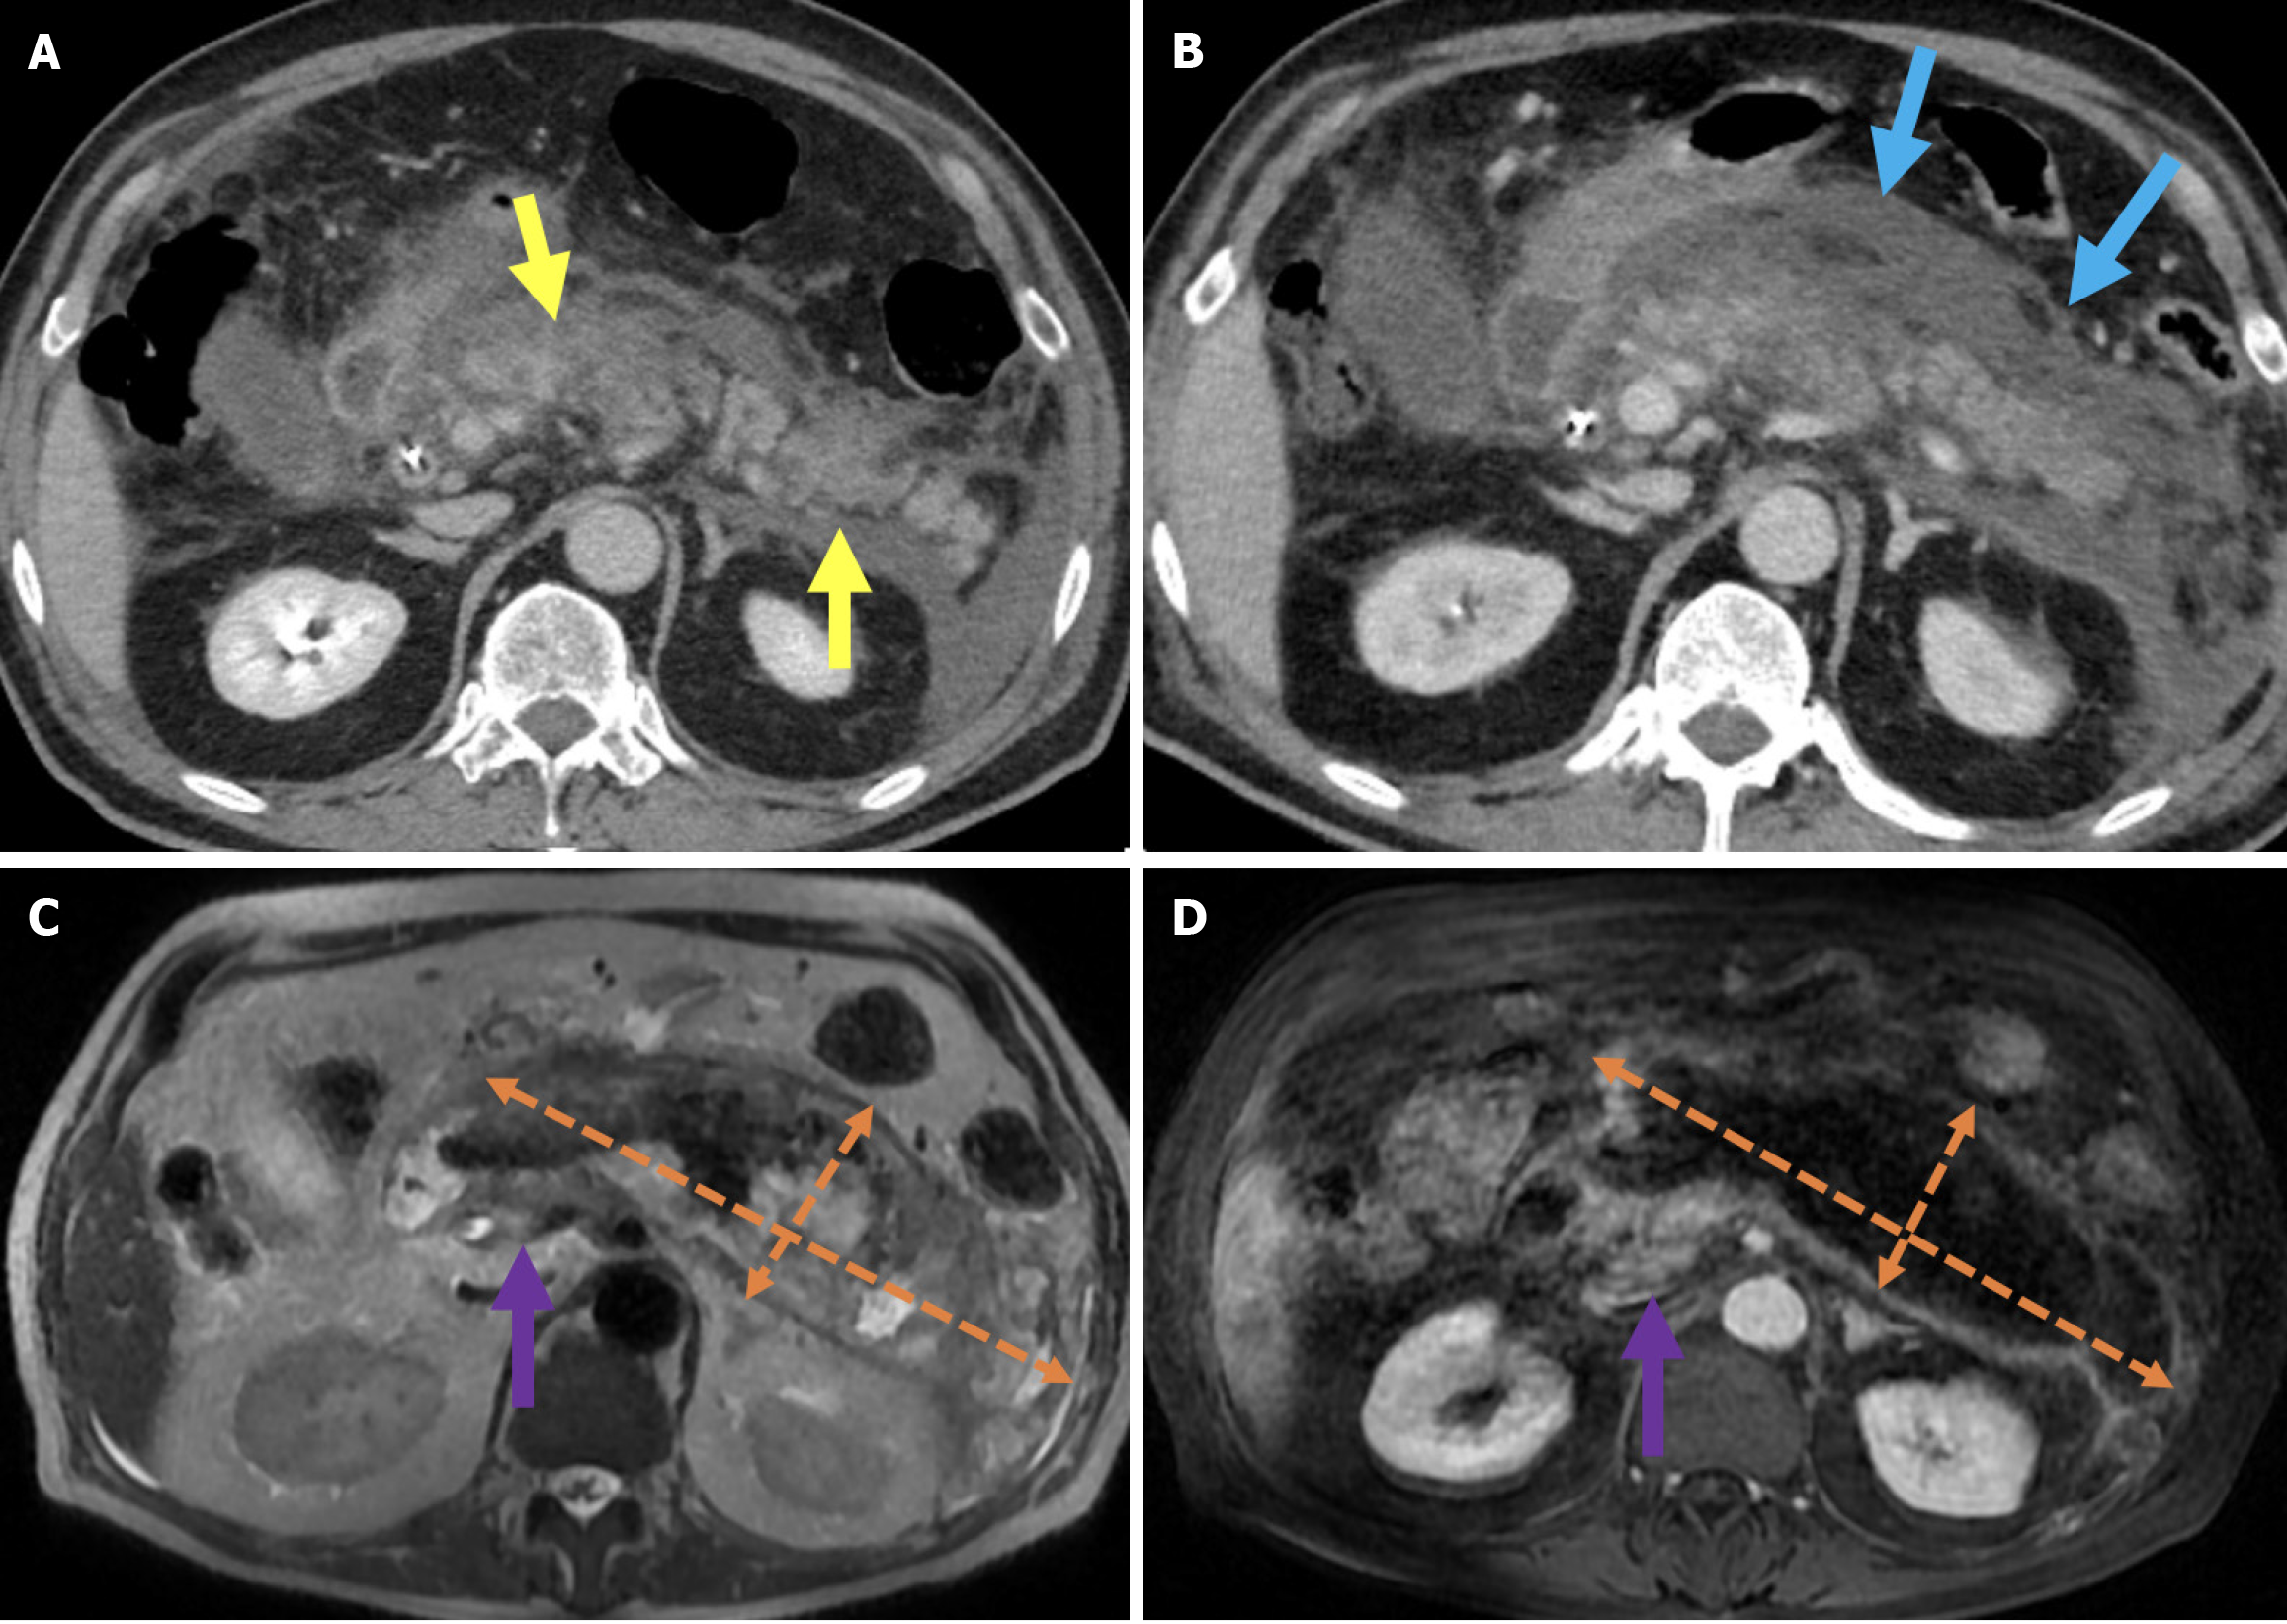

The revised Atlanta classification recognizes two primary forms of acute pancreatitis: NP and interstitial edematous pancreatitis (IEP). NP tends to follow a more severe clinical course with higher rates of infection, organ failure, and mortality. Imaging reveals hypoperfused or non-enhancing areas indicating NP or peripancreatic necrosis. Early collections (within 4 weeks) are referred to as acute necrotic collections. Once encapsulated after 4 weeks, they are known as walled-off necrosis (Figure 3)[23]. IEP is characterized by a diffusely enlarged pancreas with homogeneous enhancement on CECT imaging without areas of necrosis and with peripancreatic fat stranding and fluid accumulation. Fluid collections observed within the first 4 weeks are termed acute peripancreatic fluid collections, while those persisting beyond 4 weeks are classified as pancreatic pseudocysts (Figures 4 and 5).

MRI with its superior soft tissue resolution offers greater accuracy for the assessment of small necrotic regions of the pancreas[33]. Although MRI is less accessible and more costly than CT, it can be used for the diagnosis and follow-up of PEP. In IEP, pancreatic enhancement is preserved, and T2-weighted images typically reveal increased signal intensity, indicating pancreatic edema and peripancreatic inflammatory changes including fat stranding and fluid collections. In NP, decreased or heterogeneous enhancement areas are seen (Figure 3)[33]. In 20% of patients with NP, necrosis is confined to the peripancreatic fat without involvement of the pancreatic parenchyma. Patients in this category usually experience a more favorable disease course compared with those with glandular necrosis but a worse outcome than in individuals with IEP[34]. MRI is superior to CT in evaluating peripancreatic fat necrosis due to its enhanced soft tissue contrast[35]. MRI and MRCP are particularly valuable in visualizing the communication between pancreatic ducts and fluid collections. They aid in the diagnosis of disconnected pancreatic duct syndrome and determining the need for surgical intervention[33,35,36].

Walled-off necrosis typically appears as a partially liquefied collection containing solid necrotic tissue and fatty debris. The advantage of MRI in soft tissue contrast over CT enhances the accuracy in assessing the solid parts of pancreatic and peripancreatic collections. As the amount of solid debris increases, the effectiveness of drainage through stents or catheters tends to decrease. Therefore, MRI is particularly useful in guiding therapeutic decisions, including the need for endoscopic necrosectomy[36].

In patients with suspected cholangitis, US is the typical initial imaging modality. It reveals intrahepatic bile duct dilatation and biliary abscesses. CT and MRI can be employed for further evaluation. Imaging findings include thickened and contrast-enhancing bile duct walls, a prominently enhancing and edematous ampulla, periportal T2 hyperintense areas, and diffusion restriction. Heterogeneous hepatic parenchymal enhancement and cholangitic abscesses may be observed (Figure 6)[43-45].

Figure 6

Figure 6 Cholangitis. A and B: Coronal (A) and axial (B) contrast-enhanced computed tomography images showed findings in a 55-year-old male patient who presented with abdominal pain, chills, and jaundice 1 week after endoscopic retrograde cholangiopancreatography. The patient’s laboratory results revealed elevated levels of gamma-glutamyl transferase, alkaline phosphatase, aspartate aminotransferase, alanine aminotransferase, bilirubin, and acute phase reactants. The patient was subsequently diagnosed with cholangitis. The common bile duct appeared dilated with thickened and enhanced walls (yellow arrows). There was also dilatation of the intrahepatic bile ducts and periductal areas of increased perfusion, likely secondary to inflammation (orange circle).

Imaging findings on US include a thick-walled, hydropic gallbladder, and pericholecystic fluid. Moreover, CT and MRI reveal abnormal gallbladder wall enhancement (Figure 7)[48].

Figure 7

Figure 7 Cholecystitis. A and B: Axial (A) and sagittal (B) contrast-enhanced computed tomography images showed findings consistent with post-endoscopic retrograde cholangiopancreatography cholecystitis in a 33-year-old female patient who presented 10 days after endoscopic retrograde cholangiopancreatography with abdominal pain, nausea, and a positive Murphy’s sign. The patient’s laboratory results revealed elevated levels of aspartate aminotransferase, alanine aminotransferase, and acute phase reactants. Imaging features included gallbladder wall thickening, increased mucosal enhancement (yellow arrows), and stranding in the pericholecystic fat (blue arrow).